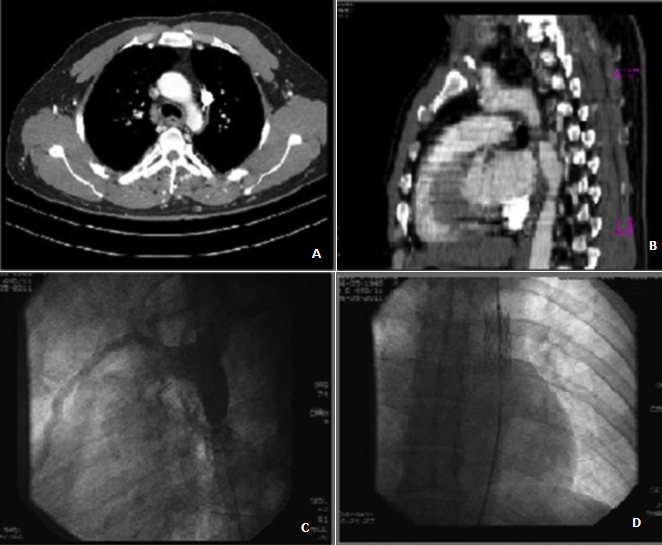

We report the case of a 45 years old man with no individual's history, suffering from hypertension recently discovered, admitted to our department for hypertensive urgencies. The clinical exam found a significant difference in blood pressure between the upper and lower limbs. The radial and ulnar pulses are present but the pulses of both lower limbs are abolished. The resting electrocardiogram recorded a regular and sinus rhythm and repolarization disorders laterally. The chest x-ray showed a normal heart volume and diffuse ribs erosions. The Transthoracic echodoppler displayed a normal left ventricular size and systolic function and a major LV enlargement. The ascending aorta was at normal size with the presence of a normal tricuspid aortic valve. The thoraco-abdominal CT (A, B) showed a coarctation of the proximal portion of the descending thoracic aorta and a double permeable superior vena cava. The patient underwent successful endovascular treatment of the coarctation with stent placement (C, D). The particularity of this observation is the late announcement of the coarctation at adult age and its association with a double superior vena cava.